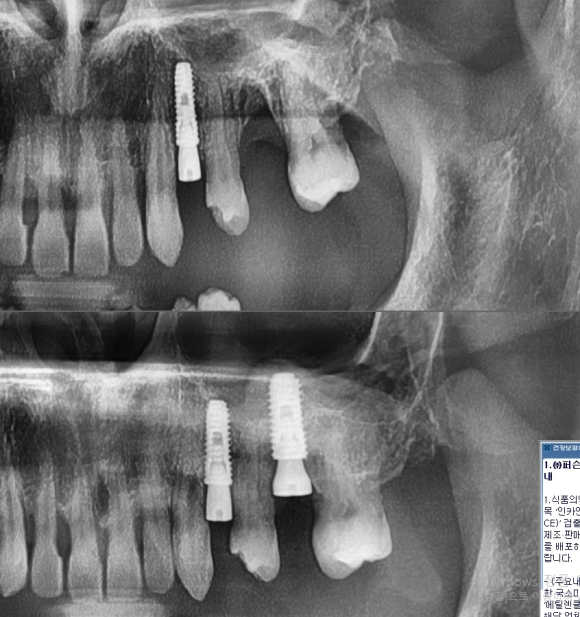

해당 환자분 오랜 만성 치아뿌리 주위염으로 인한 치아지지 상실로

치아가 많이 흔들리고 저작 시 통증이 유발되어

발치 후 임플란트를 진행하였습니다.

오랜 기간 염증으로 인하여 잇몸뼈의 소실이 심한 케이스였으나

상악동 수술과 뼈이식으로 성공적으로 임플란트 식립이 되었습니다.

이제, 없던 뼈가 만들어져야하는 충분한 기다림이 필요하겠습니다.

5개월 뒤 만들어진 뼈의 양과 질을 평가 후

받아들여질 수 있을만한 뼈가 생성이 되었다면

보철시기를 결정할 것입니다.